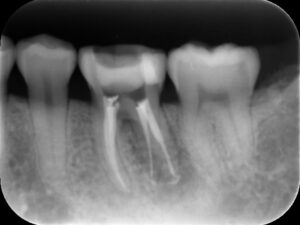

初診時レントゲン。他院にて根管治療を数か月行っているが痛みが続いていると訴えて来院。根管内には依然に詰めた薬がまだ残っているように見える。根尖部の骨破壊はほとんど認めない。

再根管治療後レントゲン。多少の違和感はあったものの、根管内部がきれいになり、排膿を認めないことから根管充填(薬を詰めること)を行った。根尖部までしっかりと薬が詰まっているのが分かる。歯根の内部がきれいな状態であれば、歯科医にはそれ以上出来ることはない。悪戯に弄り過ぎてはいけない。